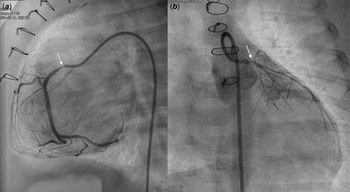

A male patient with d-transposition of the great arteries with an intact ventricular septum underwent arterial switch operation at 7 days of age. He had abnormal coronary arteries, both arising from a single coronary sinus, and an unusual left coronary artery with an intramural course. Both coronary arteries were re-implanted successfully by unroofing the left coronary artery ostium. One month after arterial switch operation, he presented to the emergency department with severe left ventricular dysfunction (left ventricle ejection fraction = 20%) and heart failure. Urgent coronary angiography confirmed severe stenosis of the proximal right coronary artery (Fig 1a) and near total occlusion of the left coronary artery ostium (Fig 1b). Emergent angioplasty of the left coronary artery ostium was performed in the 5-kg-body-weight patient. After post-operative recovery and improvement of left ventricular function, ventricular dysfunction (ejection fraction = 15%) re-developed at 4 months of age, approximately 2 months after the second operation. Percutaneous coronary intervention was planned in the infant, now 7 kg of body weight, to be performed by a paediatric cardiologist and adult interventional cardiologist. Elective extracorporeal membrane oxygenation of the right internal jugular vein-right common carotid artery was performed before percutaneous coronary intervention. Coronary angiography showed 95% segmental stenosis of the left coronary artery and 99% diffuse stenosis of the right coronary artery. Left coronary artery angioplasty with a 2.0 × 15-mm Maverick balloon was conducted successfully at 8 atm (Fig 2a), and 30% residual stenosis without dissection was confirmed (Fig 2b). Due to the unusual position of the right coronary artery, a 5-Fr JR 4.0 guiding catheter was reshaped and engaged properly with the right coronary artery. Runthrough and Sion guidewires were used to cross the lesion. Because 50% residual stenosis was found in the right coronary artery after angioplasty with 2.0 × 15-mm Maverick balloon at 12 atm, stent implantation with a 2.25 × 26-mm Orsiro stent at 12 atm was performed successfully (Fig 2c). After post-adjunctive balloon dilatation with 2.5 × 8-mm NC balloon, 10% residual stenosis in the right coronary artery was confirmed without dissection (Fig 2d). The total fluoroscopy time was 85 minutes. The patient was weaned successfully from extracorporeal membrane oxygenation the next day. Echocardiography at 7 days after percutaneous coronary intervention showed recovered ventricular contraction (left ventricle ejection fraction = 60%) but dilated left ventricle. The patient’s symptoms were relieved, and he was discharged on dual antiplatelet therapy with aspirin and clopidogrel. No complications related to femoral arterial cannulation in such a small patient were detected.

Figure 1. Angiography at one month after ASO revealed severe stenosis (thin arrow) of the proximal RCA ( a ) and nearly total occlusion (thin arrow) of the LCA ostium ( b ). ASO: arterial switch operation, RCA: right coronary artery, LCA: left coronary artery.